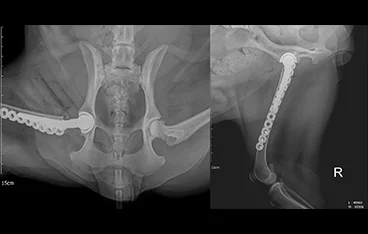

• 골반골절

• 골반골절 수술 전

골반골절 수술 후